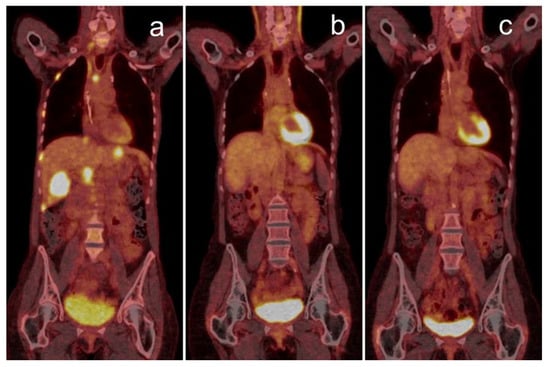

- Iravani, A.; Osman, M.M.; Weppler, A.M.; Wallace, R.; Galligan, A.; Lasocki, A.; Hunter, M.O.; Akhurst, T.; Hofman, M.S.; Lau, P.K.H.; et al. FDG PET/CT for tumoral and systemic immune response monitoring of advanced melanoma during first-line combination ipilimumab and nivolumab treatment. Eur. J. Nucl. Med. Mol. Imaging 2020, 47, 2776–2786. [Google Scholar] [CrossRef] [PubMed]

- Sachpekidis, C.; Larribère, L.; Kopp-Schneider, A.; Hassel, J.C.; Dimitrakopoulou-Strauss, A. Can benign lymphoid tissue changes in 18F-FDG PET/CT predict response to immunotherapy in metastatic melanoma? Cancer Immunol. Immunother. 2019, 68, 297–303. [Google Scholar] [CrossRef]

- Wong, A.; Callahan, J.; Keyaerts, M.; Neyns, B.; Mangana, J.; Aberle, S.; Herschtal, A.; Fullerton, S.; Milne, D.; Iravani, A.; et al. 18F-FDG PET/CT based spleen to liver ratio associates with clinical outcome to ipilimumab in patients with metastatic melanoma. Cancer Imaging 2020, 20, 36. [Google Scholar] [CrossRef]